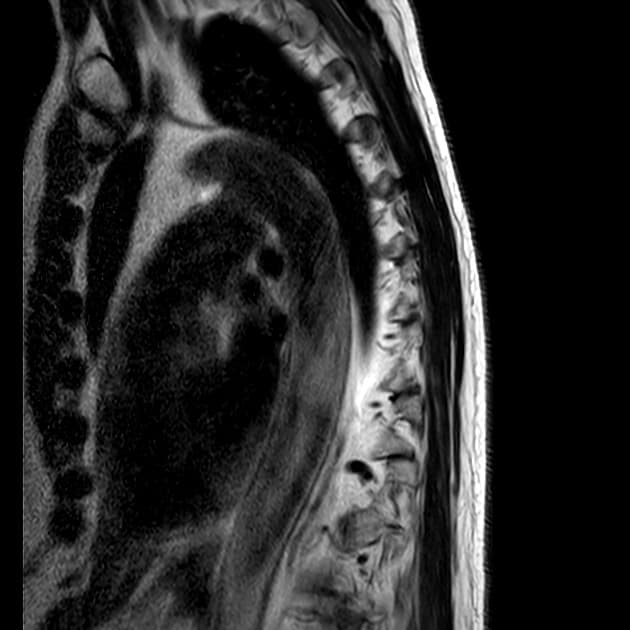

Sagittal T2

MRI•Sagittal T2•1 Img

- Phì đại rõ rệt bán cầu tiểu não phải mà không có khối khu trú hay thay đổi dạng nang.

- Bán cầu này đồng tín hiệu trên hình ảnh trọng T1 và tăng tín hiệu trên hình ảnh trọng T2, không thấy tăng quang bất thường.

- Có hiệu ứng khối dương tính rõ rệt tại hố sọ sau, nơi mà đã bị giãn rộng.

- Não thất bốn bị xóa mờ và có giãn các não thất bên (thấy rõ nhất trên hình ảnh T2 cắt ngang).

- "Chụp cộng hưởng từ thường cho thấy tổn thương tiểu não không tăng quang, tín hiệu tăng trên hình ảnh trọng T2, có hiệu ứng khối và xóa mờ não thất bốn, thường thấy hình ảnh 'sọc hổ' trên cắt ngang."

Bệnh Lhermitte-Duclos, còn gọi là u tăng sản hạch thần kinh tiểu não, là tình trạng tăng trưởng bất thường lành tính của vỏ tiểu não. Đây là dấu hiệu đặc trưng của hội chứng Cowden, một rối loạn trội trên nhiễm sắc thể thường do đột biến gen PTEN, làm tăng nguy cơ u tổ chức nhân và ung thư vú, tuyến giáp, nội mạc tử cung. Hình ảnh học thường rất điển hình: bán cầu tiểu não giãn to lan tỏa, tăng tín hiệu trên trọng T2, không tăng quang, gây hiệu ứng khối và giãn não thất do tắc nghẽn. Hình ảnh 'sọc hổ' trên cộng hưởng từ T2 cắt ngang – do các lá tiểu não xen kẽ tăng và đồng tín hiệu – là đặc hiệu. Chẩn đoán chủ yếu dựa vào hình ảnh học, nhưng sinh thiết có thể cần thiết trong các trường hợp không điển hình. Điều trị bao gồm theo dõi các ung thư liên quan, xử trí triệu chứng và giải áp phẫu thuật nếu có hiệu ứng khối hoặc giãn não thất nặng.